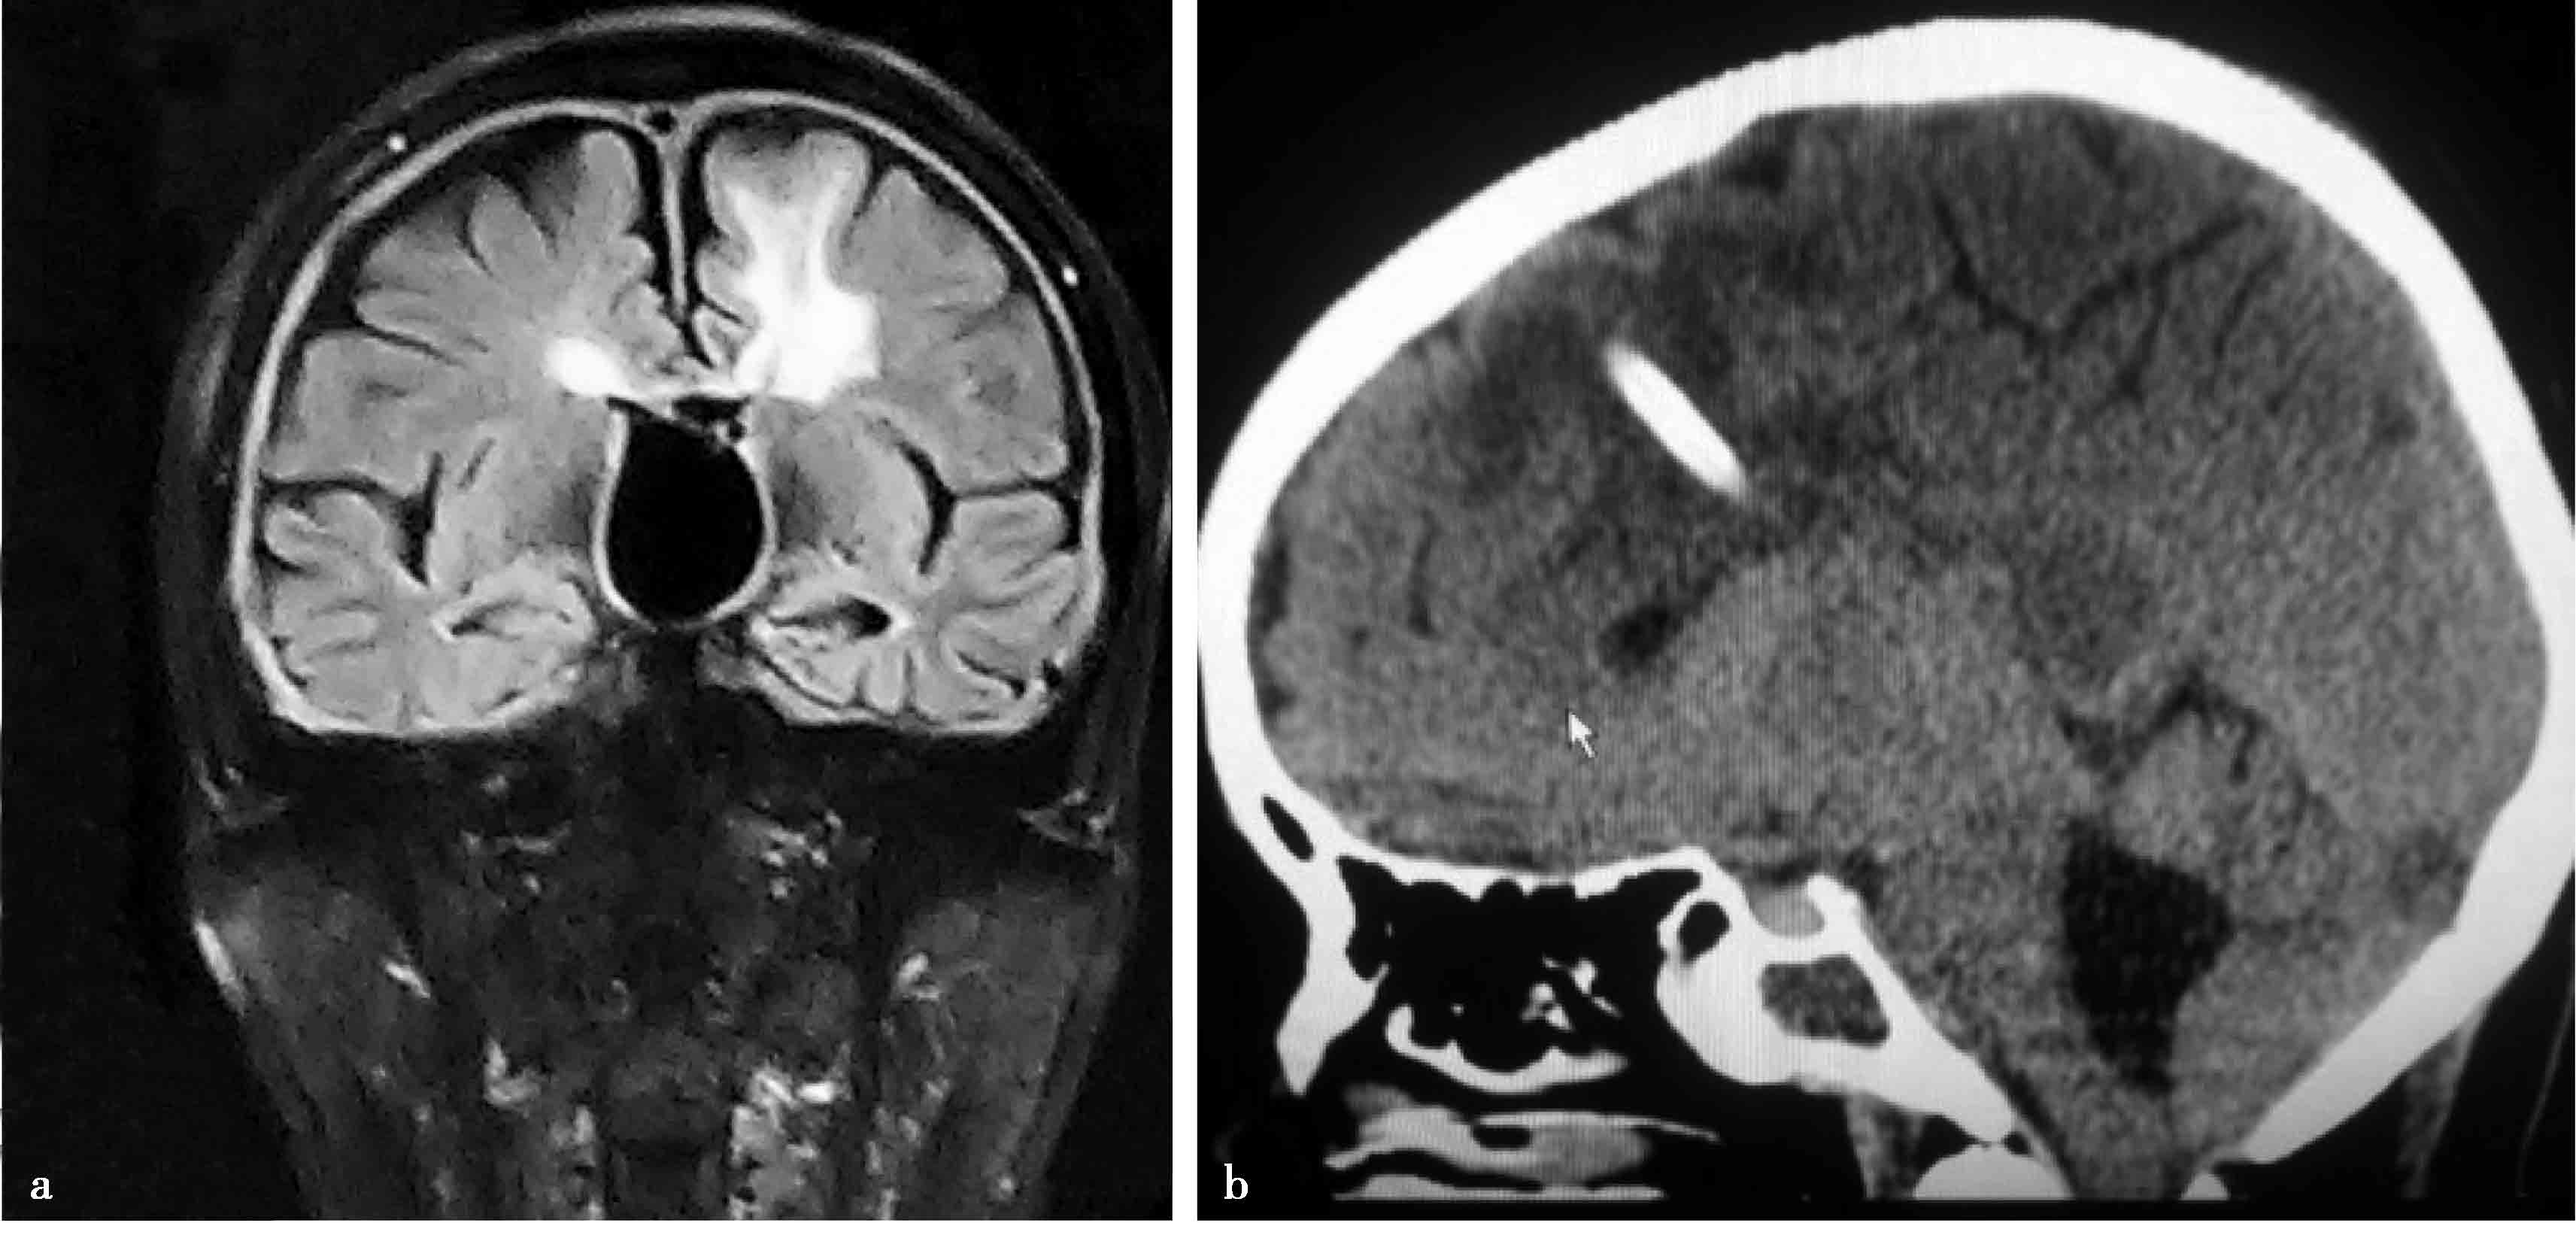

图3-1-1-1 出血后脑积水的脑室演变

a.发病时头颅CT:脑室内血肿呈高密度;b.发病12天后复查CT:血肿已呈低密度;c.发病5个月后头颅MRI:脑室明显扩张,脑室内未见异常信号;d.内镜下探查见脑室内仍有陈旧血斑及含铁血黄素沉积

图3-1-1-2 第三脑室底下疝的神经影

a.头颅MRI矢状位片所见,酷似鞍上池囊肿;b.内镜下探查,证实长期脑积水所致第三脑室底深度下疝